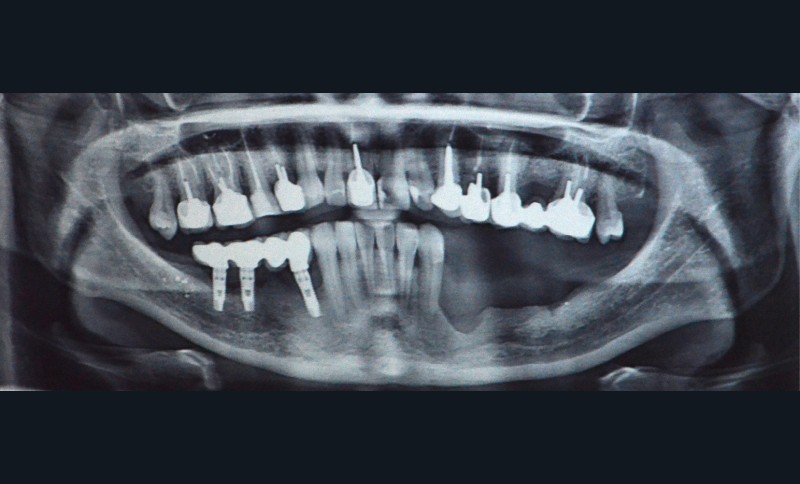

Il s’agit d’une jeune patiente 38 ans ayant présenté une perte osseuse à la suite de péri-implantite. Les implants ont été déposés. La patiente présente une atrophie mandibulaire postérieure classée Cawood V (fig. 1).